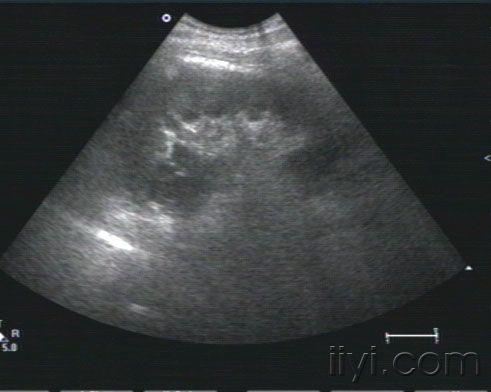

右肾挫伤,肾盂积血 - 超声医学讨论版 - 爱爱医医学论坛

图片尺寸768x576